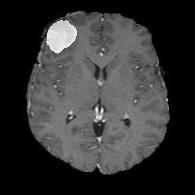

(a) (b) (c) (d) (e)

Comparison to Competing Methods:

We have compared the performance of our model against the most popular deep learning-based semantic segmentation networks, U-Net [9] and V-Net [7] (Fig. 3). Our model outperforms both by a considerable margin in all evaluation metrics. In particular, U-Net performs poorly in most cases due to the high false positive of its segmentation predictions, as well as the imprecision of its boundaries. The powerful residual block in the V-Net architecture seems to alleviate these issues to some extent, but V-Net also fails to produce high-quality boundary predictions. The emphasis of learning useful edge-related information during the training of our network appears to effectively regularize the network such that boundary accuracy is improved.